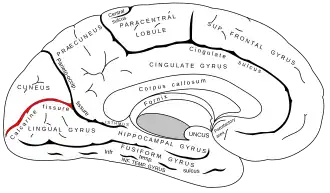

Le sillon calcarin (anciennement scissure calcarine) est un sillon de la face interne du lobe occipital du cortex. C'est un sillon large et profond, d'environ 85 mm de longueur et de 16 mm de profondeur.

Le sillon calcarin commence près du pôle occipital par deux rameaux convergents et court vers le haut et vers l'avant jusqu'à un point situé légèrement au-dessous du splénium du corps calleux, où il est rejoint et interrompu à angle aigu par la partie médiale de la scissure pariéto-occipitale. La partie antérieure de la scissure calcarine donne naissance au renflement du calcar avis dans la corne postérieure du ventricule latéral.

| Face interne | Vue inféro-interne du cortex, d'après une pièce anatomique |